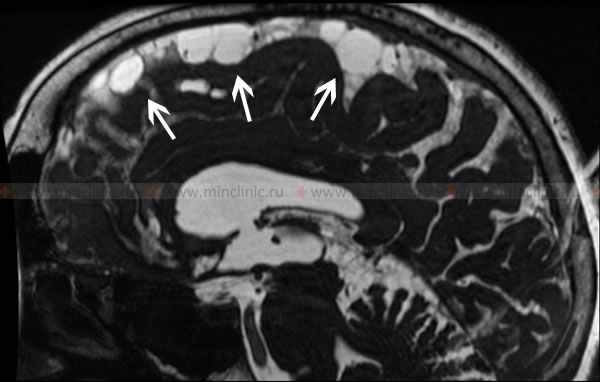

В тяжелых случаях могут возникнуть генерализованные судорожные приступы вплоть до развития эпилептического статуса. Важное значение для выявления локализации очага арахноидита имеют электроэнцефалография и МРТ головного мозга.

МРТ головного мозга в T2 режиме демонстрирует скопление спинномозговой жидкости в конвекситальном пространстве при церебральном арахноидите (указано стрелками).

Увеличенные боковые желудочке на МРТ головного мозга при гидроцефалии с арахноидитом оболочек головного мозга.